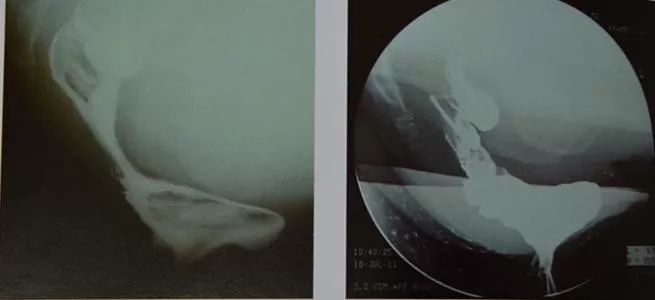

2、排粪造影

在钡剂显影下可见直肠前壁向前突出,钡剂通过肛管困难。可分为三度:即轻度,前突深度为0.6~1.5cm;中度为1.6~3cm,重度≥3.1cm。